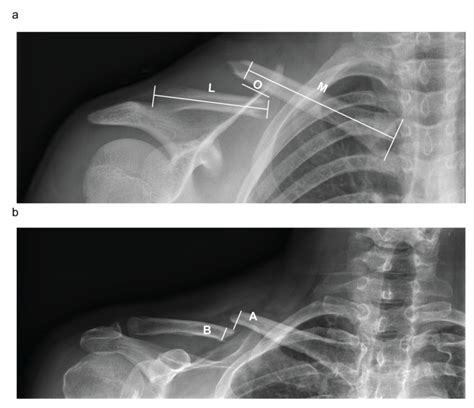

• Radiographic Evidence: An X-ray is the gold standard. A doctor looks for "bridging callus," which indicates that new bone has grown across the fracture site.

Achieving a healed broken clavicle is a milestone that signifies the end of a difficult period, but it is also a transition toward long-term maintenance. By respecting the timeline of bone regeneration and committing to the necessary physical therapy, you ensure that your shoulder remains stable and strong for years to come. Listen to your body, rely on objective diagnostic tools like X-rays to guide your progress, and do not rush the transition back to high-intensity activities. With the right care and patience, most individuals return to their full baseline of strength and daily function, putting the injury firmly in the past.